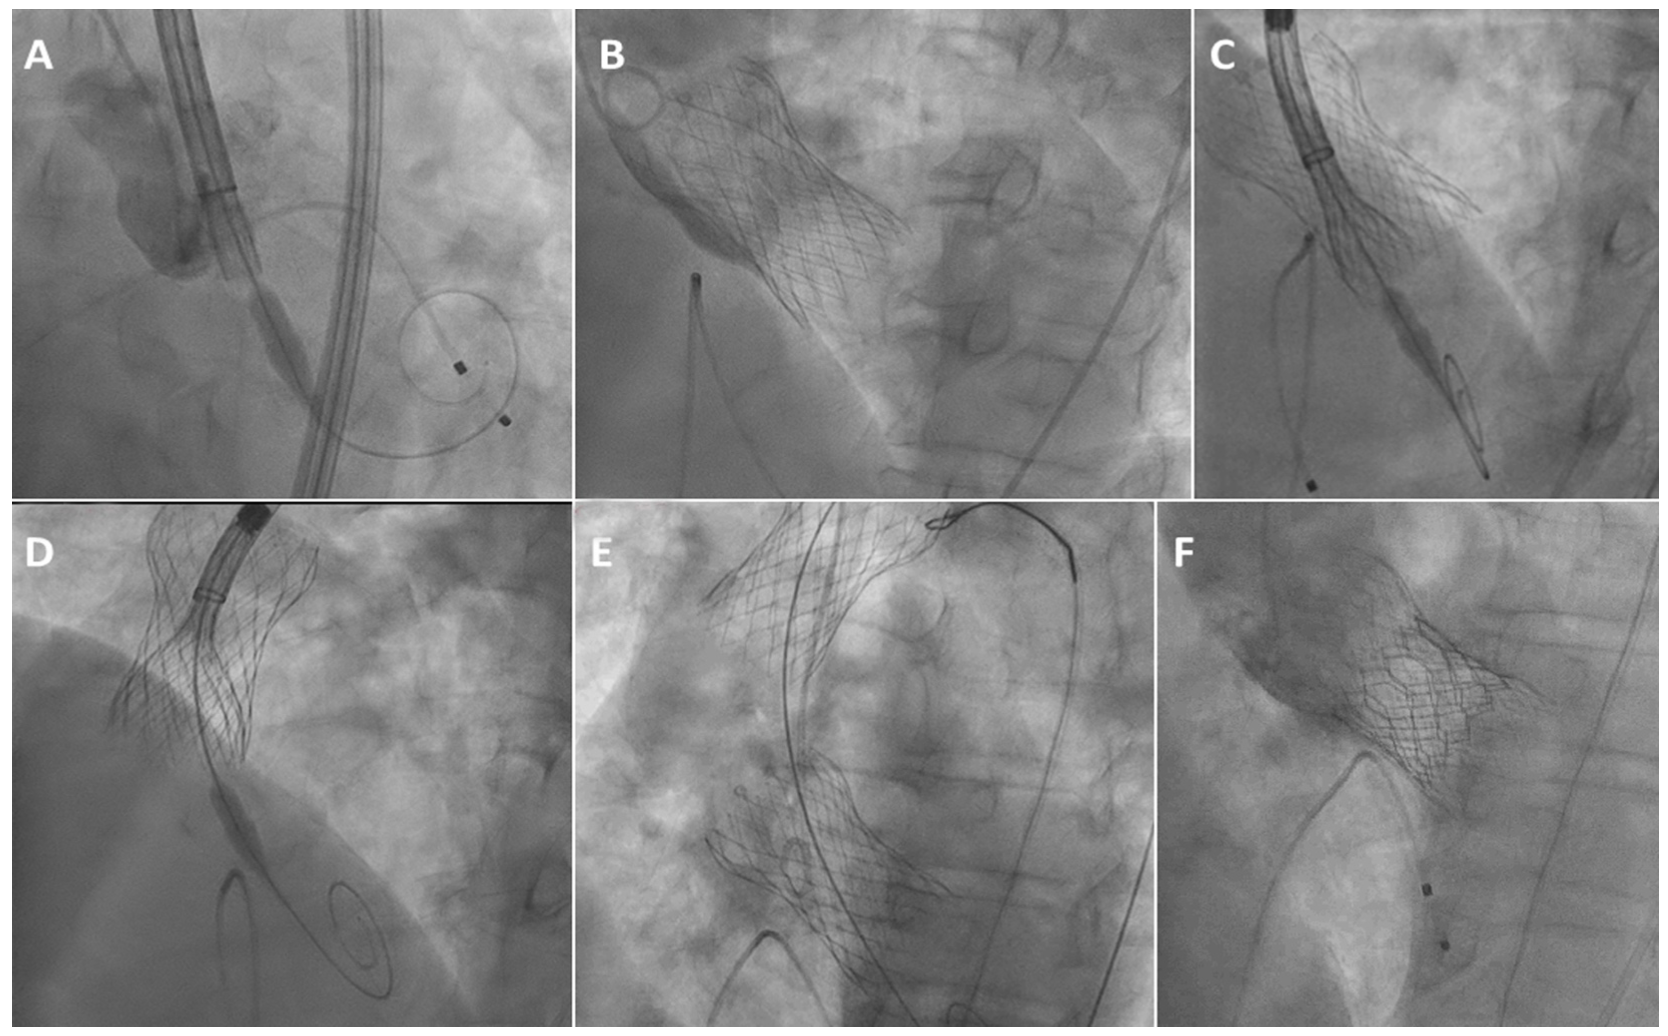

(A) Valve #1 initially positioned 5 mm below the annulus; (B) Valve #1 implanted 16 mm below the annulus; (C) Positioning valve #2 within valve #1; (D) Valve embolization: partially-released valve #2 within fully-released valve #1; (E) Valve #1 snared in the ascending aorta and valve #2 implanted 16 mm below the annulus; (F) Valve #3 implanted within valve #2.

Reprinted with permission from Sliman H, Eitan A, Jaffe R. J Invasive Cardiol. 2023 May;35(5):E277-E278.